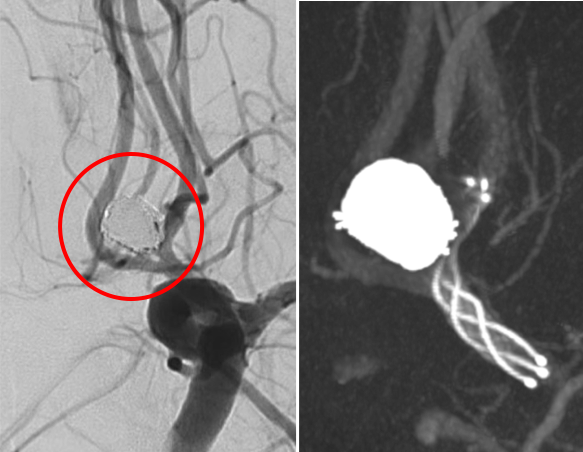

脳動脈瘤コイル塞栓術

脳動脈瘤にマイクロカテーテルという細いカテーテルを挿入し、動脈瘤の中にコイル(プラチナ製の細い糸)を充填して、動脈瘤内に血流が入り込まないようにする治療法です。開頭する必要がありません(低侵襲)。また脳動脈瘤コイル塞栓支援用ステントを使用することで、これまで脳血管内治療が困難であった動脈瘤も治療できるようになってきました。当院では積極的に脳動脈瘤コイル塞栓術を第一選択として治療を行っております。

破裂内頚動脈瘤

術前の造影写真です。〇内に脳動脈瘤が造影されています。

術後の造影写真です。主幹動脈は温存できており、動脈瘤は造影されなくなっています。

術後4週間、動脈瘤の再発はありません。

術後6か月、動脈瘤は完全に消失しています。